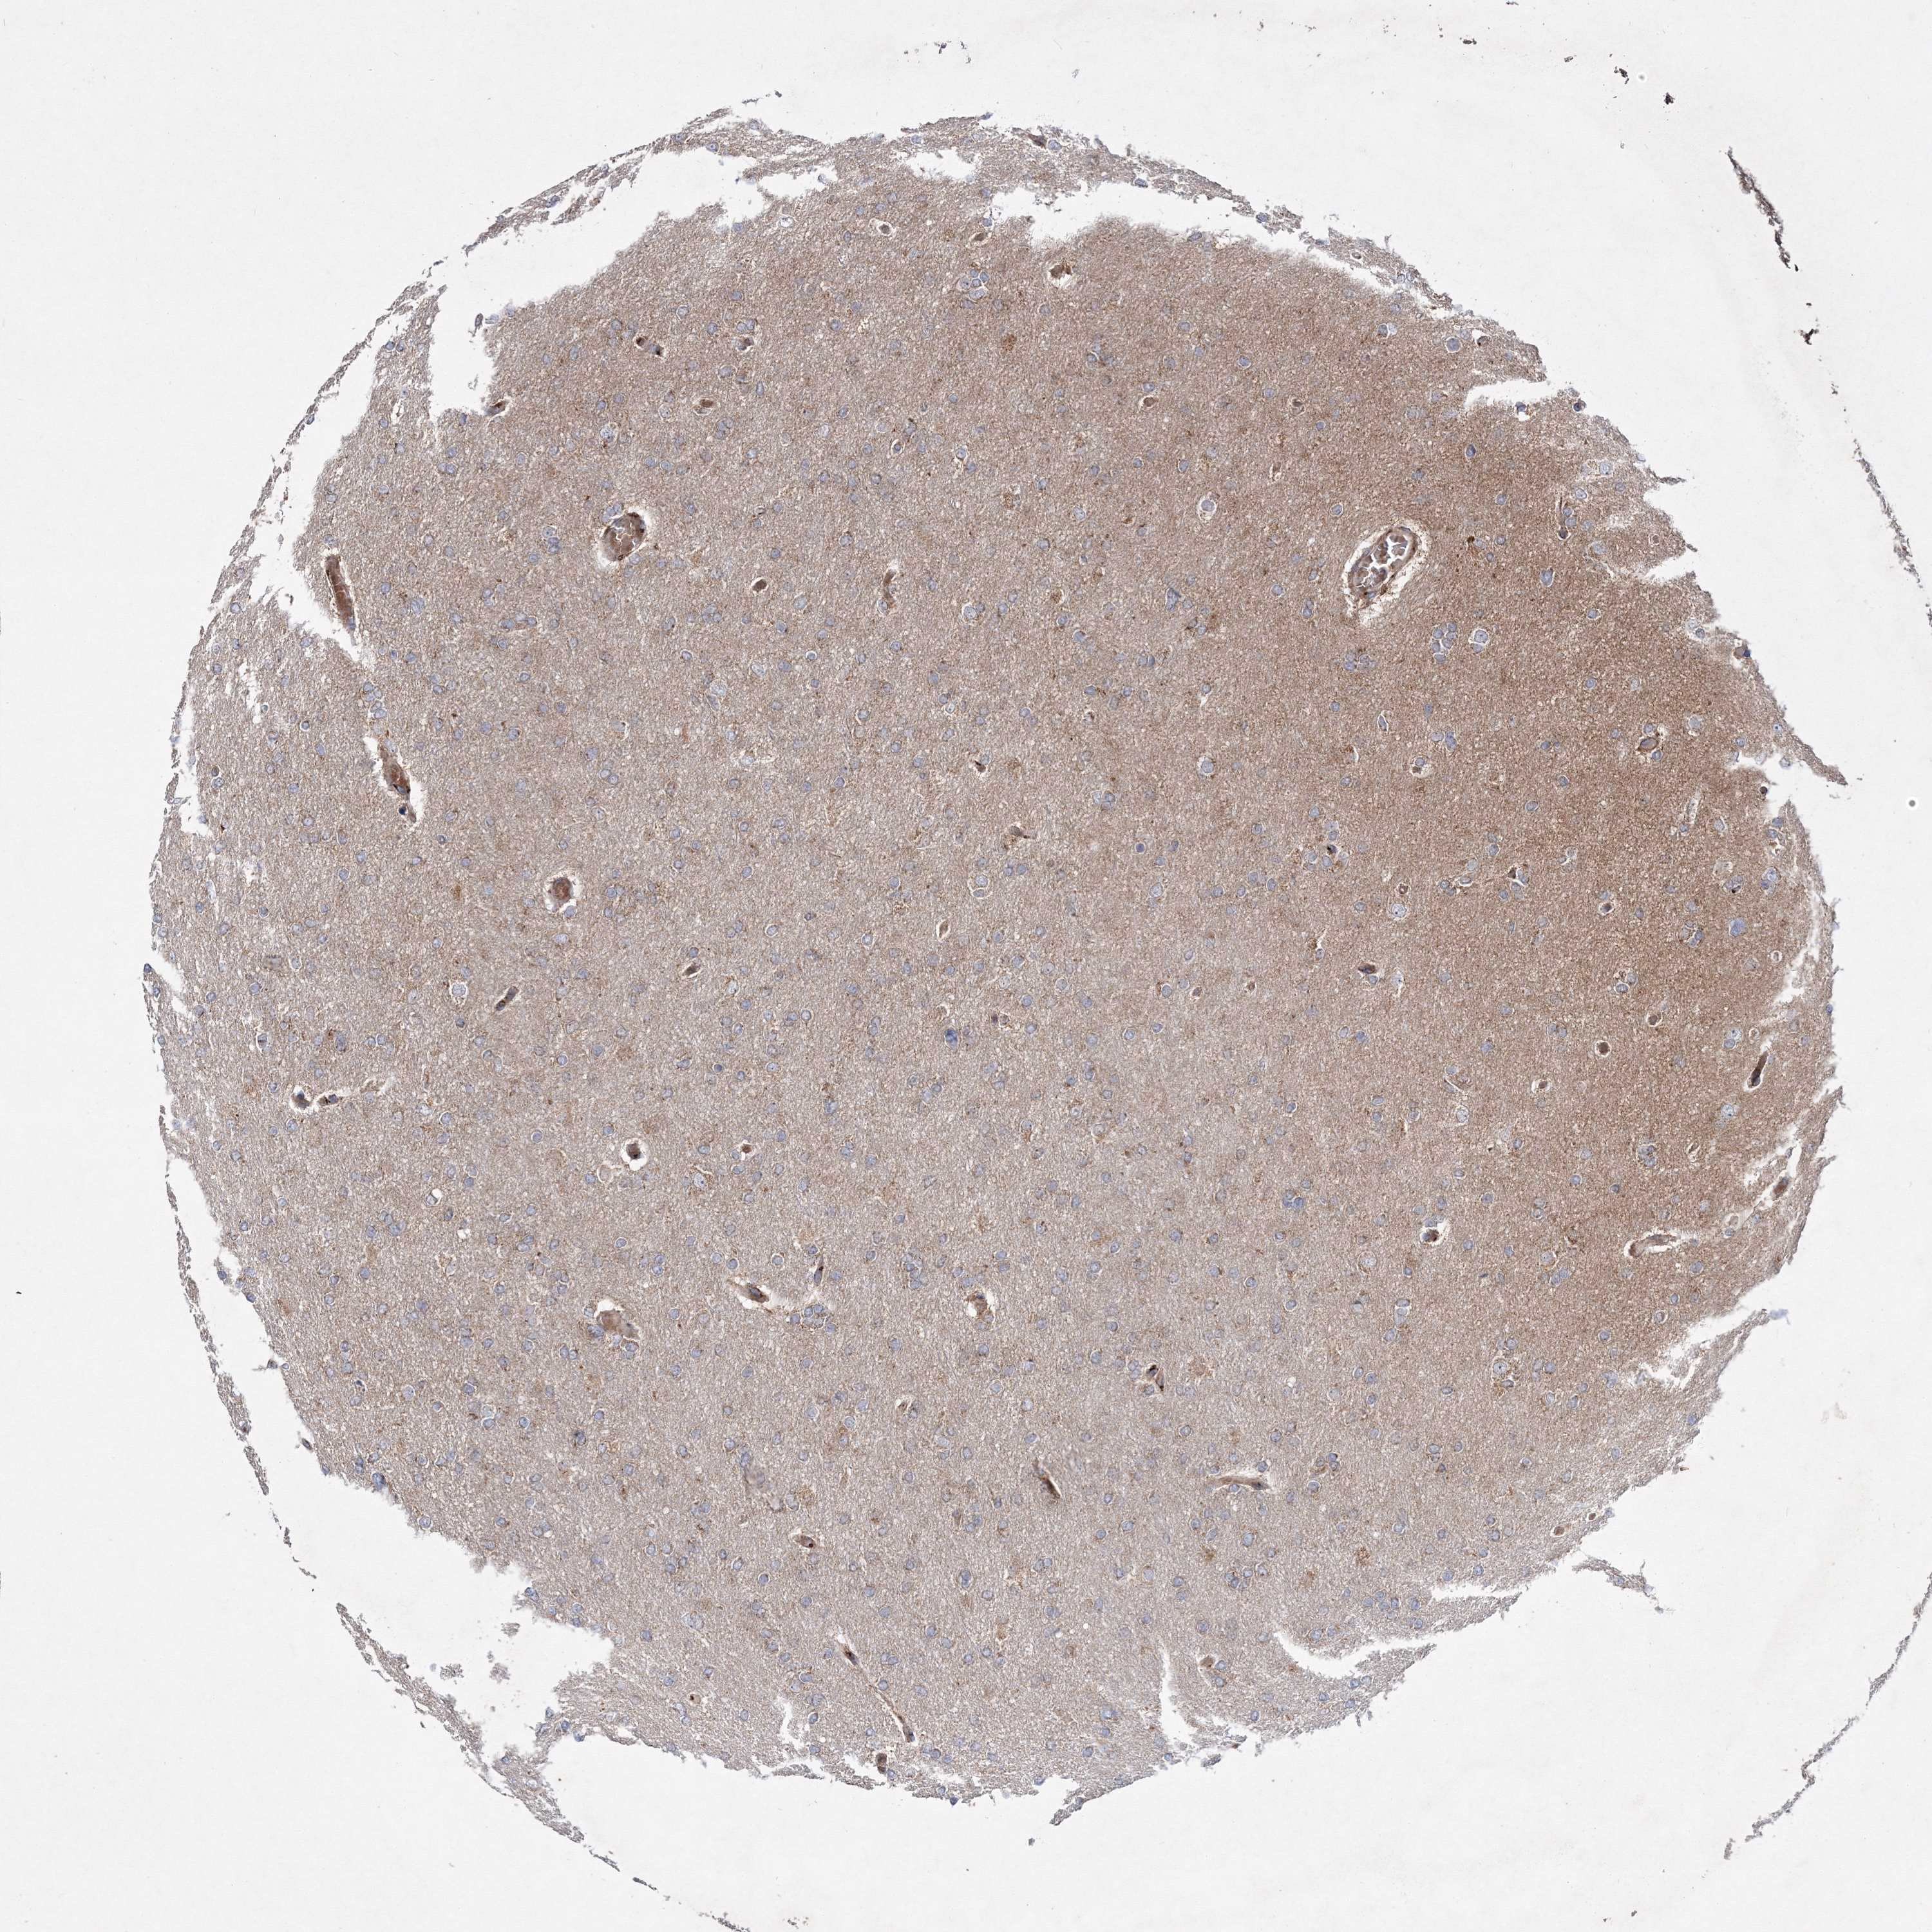

GLIOMA - Protein expressioni

A mouse-over function shows sample information and annotation data. Click on an image to view it in a full screen mode. Samples can be filtered based on level of antibody staining by selecting one or several of the following categories: high, medium, low and not detected. The assay and annotation is described here.

Note that samples used for immunohistochemistry by the Human Protein Atlas do not correspond to samples in the TCGA dataset.

Antibody stainingi

Antibody staining in the annotated cell types in the current human tissue is reported as not detected, low, medium, or high, based on conventional immunohistochemistry profiling in selected tissues. This score is based on the combination of the staining intensity and fraction of stained cells.

Each image is clickable and will lead to virtual microscopy that enables deeper exploration of all samples and also displays staining intensity scores, fraction scores and subcellular localization as well as patient and tissue information for each sample.

Antibody HPA036923

Antibody HPA036924

Staining

High

Medium

Low

Not detected

Intensity

Strong

Moderate

Weak

Negative

Quantity

>75%

75%-25%

<25%

None

Location

Nuclear

Cytoplasmic/membranous

Cytoplasmic/membranous,nuclear

Glioma, malignant, High grade

Glioma, malignant, Low grade

Glioblastoma, NOS